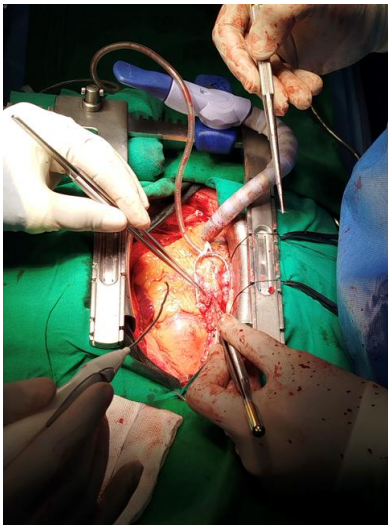

Induction was done as per the standard protocol for CABG patients. After median sternotomy, right internal mammary artery (RIMA) was harvested. RIMA was anastomosed to morphological LAD and saphenous venous graft was anastomosed to the Obtuse Marginal branch and the posterior descending artery to achieve complete Revascularization. The operating surgeon was on the left side of the patient while operating. After surgery, the patient was shifted to postoperative intensive care unit, extubated after 4 h of mechanical ventilation.

Figure 7: SVG is being anastomosed with PDA and the surgeon is standing on the right side.

Figure 8: This is RIMA to LAD with the surgeon standing on the right side

Figure 9: SVG is being anastomosed with PDA and the surgeon is standing on the right side.

Figure 7

Figure 8

Figure 9